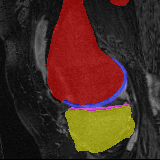

Moving Target Mono-0 Mono-5 DA-1 DA-5 Mono-200 Refer to caption Refer to caption Refer to caption Refer to caption Refer to caption Refer to caption Refer to caption Refer to caption Refer to caption Refer to caption Refer to caption Refer to caption Refer to caption Refer to caption

Figure 2:  Examples of knee MRI registration (top) and brain MRI segmentation (bottom) results. Top: The first two columns are the moving image/segmentation and the target image/segmentation followed by the warped moving images (with deformation grids)/segmentations by different models. Bottom left to right: original image, manual segmentation, and predictions of various models. Mono-i𝑖i and DA-i𝑖i represent the mono- and DA models with i𝑖i manual segmentations respectively.

Moving Target Mono-0 Mono-21 DA-1 DA-21 Mono-65 Refer to caption Refer to caption Refer to caption Refer to caption Refer to caption Refer to caption Refer to caption Refer to caption Refer to caption Refer to caption Refer to caption Refer to caption Refer to caption Refer to caption

Figure 4: Examples of brain MRI registration (top) and knee MRI segmentation (bottom) results. Top: The first two columns are the moving image/segmentation and the target image/segmentation followed by the warped moving images/segmentations by different models. Bottom left to right: original image, manual segmentation, and predictions of various models. Mono-i𝑖i and DA-i𝑖i represent the mono- and DA models trained with i𝑖i manual segmentations respectively.